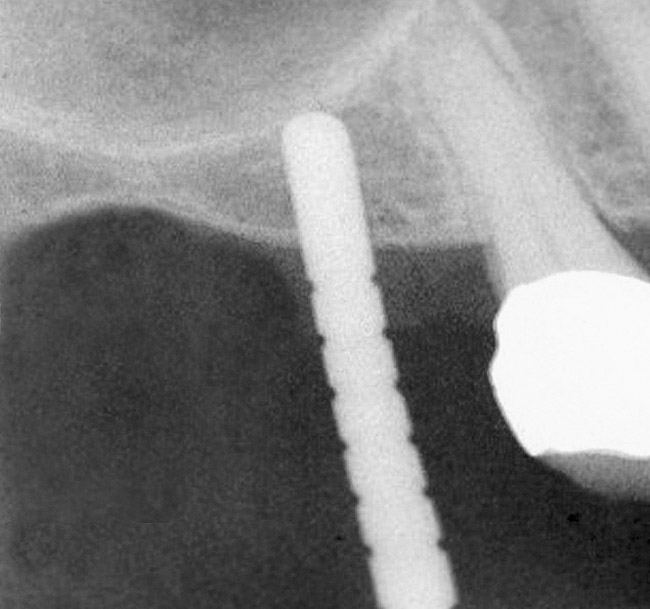

The sinus floor elevation technique can be used when a tooth is extracted and there is not enough bone height to support an immediate implant (Figure 8, Figure 9 and Figure 10, Figure 11).32

Slanted Sinus Floor

Figure 9: After the extraction, a 2.1-mm twist drill was used to drill within 1 mm of the subantral floor. A guide pin was placed and a radiograph was taken to ascertain if the drill stopped within 1 mm of the subantral floor.

Figure 9

Figure 10  The osteotomy was completed with the 2.1-, 2.8-, and 3.5-mm twist drills without penetrating into the sinus. After infracturing the subantral wall with a 3.5-mm osteotome, bone was added and the presence of a dome was confirmed with a radiograph.

Figure 10

Figure 11  Insertion of a 4.8-mm implant, which fit snugly and increased the surface area for future osseointegration

Figure 11